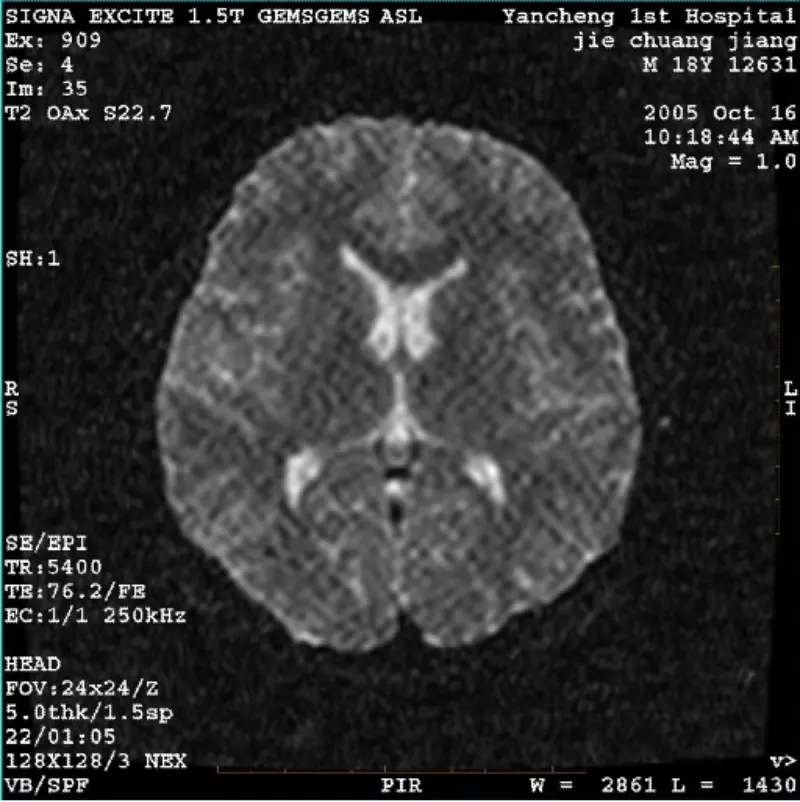

Magbasa paSYSTEM: 1.5T Signa Twin Excite II (Software Version 11.0M4) PROBLEMA/SYMPTO DWI (Zoom mode at buong mode) at fiesta (zoom mode at buong mode) na may larawan nakikitang reticulate o corduroy artifact kahit na gamit ang body coil o ulo coil, parang normal ang ibang routine na imahe